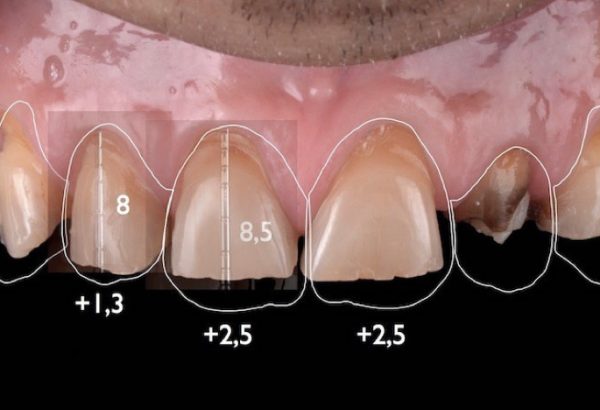

Digital Smile Designing is a cutting-edge dental technology that allows us to digitally plan and visualize your ideal smile before any treatment begins. Using high-resolution images, facial analysis, and advanced software, we design a smile that harmonizes perfectly with your facial features, personality, and expectations.